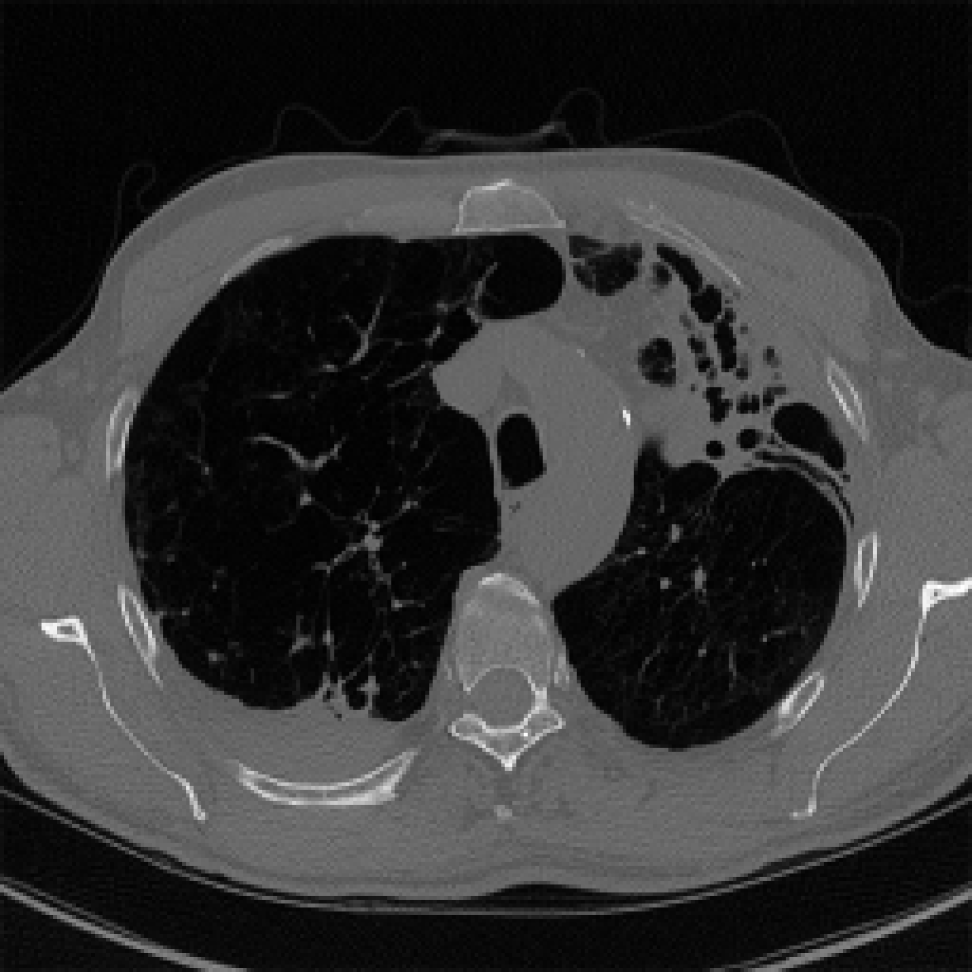

For the binary disease classification/survival prediction tasks, we used a conservative approach, thresholding the voxels at -570 HU and using morphological closing and opening operations to create smooth lung masks that contain lung parenchyma and air. To further include pathological signs such as fungus balls and pleura-thickening, we refined the approach from [4] and [5]. First, we define a set of markers. To do so, pixels are thresholded at -570 HU and connected components are extracted, while removing the smallest ones. These connected components provide internal markers. Then, we define intermediate and external markers, via morphological dilation of internal markers with structuring elements of radius 10 and 35 pixels, respectively. These markers define the spatial extent of the region where lung tissues can be added to the threshold-based segmentation. To find the lung structures to add, a watershed segmentation (Fig. 2(b)) is used, with seeds generated with a Sobel-filter edge map. It returns large homogeneous connected regions but still excludes some diseased structure with soft-tissue like attenuation values. A top-hat transform (Fig. 2(c)) is used, where the occluded region is initially morphologically closed and then the difference between the original and the closed structure is added to the watershed mask. The final segmentation mask (Fig. 2(d)) is generated after closing the remaining holes.

Refer to caption

(a) Axial slice

(b) Watershed

(c) Outline

(d) Closing

Fig. 2: Illustrations of the segmentation of the lung area